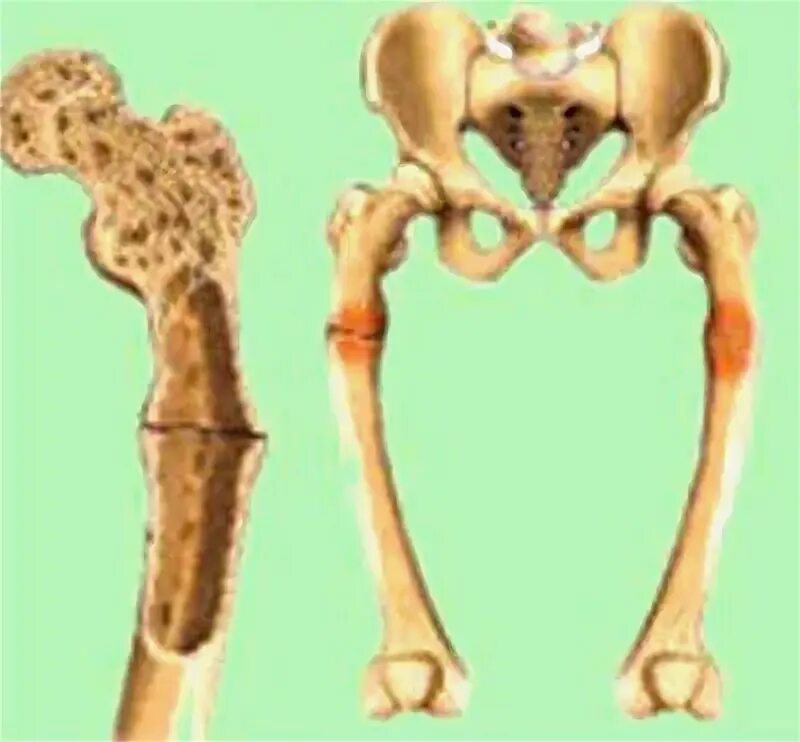

Рахит у животных